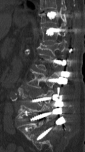

Lomber dinamik stabilizasyon

Ağustos         2022     Lomber enstruman yetmezliği ve dinamik stabilizasyonla çözümü